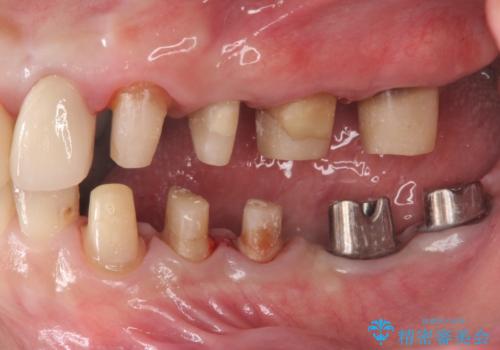

- 「少しずつ色々な箇所が悪くなり、歯医者に通い続けている。全ての歯を長持ちするような状態にできるような治療を受けたい。」、と全顎・総合的な治療を希望され来院されました。

根管治療・矯正治療・歯周外科・セラミック補綴を含む様々な治療オプションを駆使し、長期間良好な状態に保てるような治療計画を立案します。

矯正治療を絡めた総合的な治療をお行なったことで、理想的な咬合関係を確立し安定した噛み合わせで仕上げることができました。

また歯周外科を行うことで歯ぐきの腫れを改善し、清掃性を高めています。